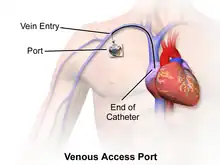

Implanted central venous catheter (ICVC, port a cath)

An implanted central venous catheter, also called a port a "cath" or "port-a-cath", is similar to a tunneled catheter, but is left entirely under the skin and is accessible via a port . Medicines are injected through the skin into the catheter. Some implanted ports contain a small reservoir that can be refilled in the same way. After being filled, the reservoir slowly releases the medicine into the bloodstream. Surgically implanted infusion ports are placed below the clavicle (infraclavicular fossa), with the catheter threaded into the heart (right atrium) through a large vein. Once implanted, the port is accessed via a "gripper" non-coring Huber-tipped needle (PowerLoc is one brand, common sizes are 0.75 and 1 inch (19 and 25 mm) length; 19 and 20 gauge. The needle assembly includes a short length of tubing and cannula) inserted directly through the skin. The clinician and patient may elect to apply a topical anesthetic before accessing the port. Ports can be used for medications, chemotherapy, and blood sampling. As ports are located completely under the skin, they are easier to maintain and have a lower risk of infection than CVC or PICC catheters.[1] An implanted port is less obtrusive than a tunneled catheter or PICC line, requires little daily care, and has less impact on the patient's day-to-day activities. Port access requires specialized equipment and training.

Ports are typically used on patients requiring periodic venous access over an extended course of therapy, then flushed regularly until surgically removed. If venous access is required on a frequent basis over a short period, a catheter having external access is more commonly used.[1]